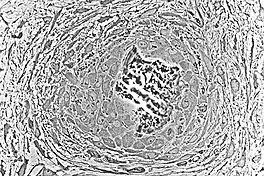

As the spicules continue to grow, they fuse with adjacent spicules and this results in the formation of trabeculae. When osteoblasts become trapped in the matrix they secrete, they differentiate into osteocytes. Osteoblasts continue to line up on the surface which increases the size. As growth continues, trabeculae become interconnected and trabecular bone is formed. The term primary spongiosa is also used to refer to the initial trabecular network.

The periosteum is formed around the trabeculae by differentiating mesenchymal cells. The primary center of ossification is the area where bone growth occurs between the periosteum and the bone. Osteogenic cells that originate from the periosteum increase appositional growth and a bone collar is formed. The bone collar is eventually mineralized and lamellar bone is formed.